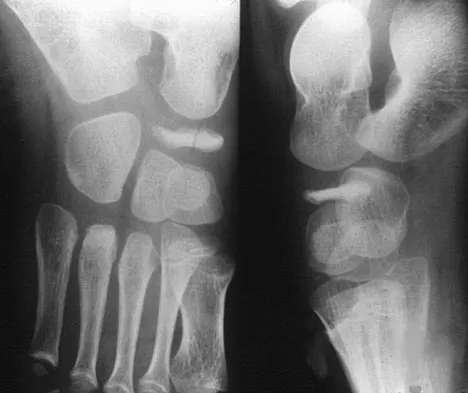

A 5-year-old boy has had pain in the right foot for the past month. Examination reveals tenderness and mild swelling in the region of the tarsal navicular. Radiographs are shown in Figure 30. Management should consist of

Explanation

The child has the classic findings of Kohler's disease or osteochondrosis of the tarsal navicular. The cause of this condition is not known, but osteonecrosis and mechanical compression have been proposed. Children generally report midfoot pain over the tarsal navicular and limping. Physical findings include tenderness, swelling, and occasionally redness in the region of the tarsal navicular. Radiographs show sclerosis and narrowing of the tarsal navicular. The natural history of the condition is spontaneous resolution and reconstitution of the navicular. Symptomatic treatment with restriction of weight bearing or casting is recommended. Karp M: Kohler's disease of the tarsal scaphoid. J Bone Joint Surg 1937;19:84-96.